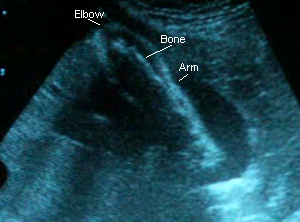

21 Weeks 1 Day

September 21, 2006: I forgot completely to ask the doctor about my AFP results, but since he didn’t mention anything I’m guessing everything’s A-OK. Baby again looks “fuller” than she did at my previous appointment, which was three weeks ago. She’s measuring perfectly and weighs approximately 0.8 lbs :). Her heartrate was at 145 BPM, though the monitor read 155. She was moving around (I got to see her little knees, feet and hands!) and Dr. C. said her head’s where my belly button is and her feet are at the bottom of my pelvis. No wonder I feel strange little jolts down there! I had glucose in my urine for the second time, but after checking me with the diabetes monitor it turns out I’m fine. Must have been the chocolate milk I drank in the morning. I’m feeling her move more after lunchtime and A LOT at 11pm. Mario finally felt her kick on 9-15-06!

Sono pic:

These are from a video I took with my camera. Thank goodness, too, because he didn’t give me pictures this time!